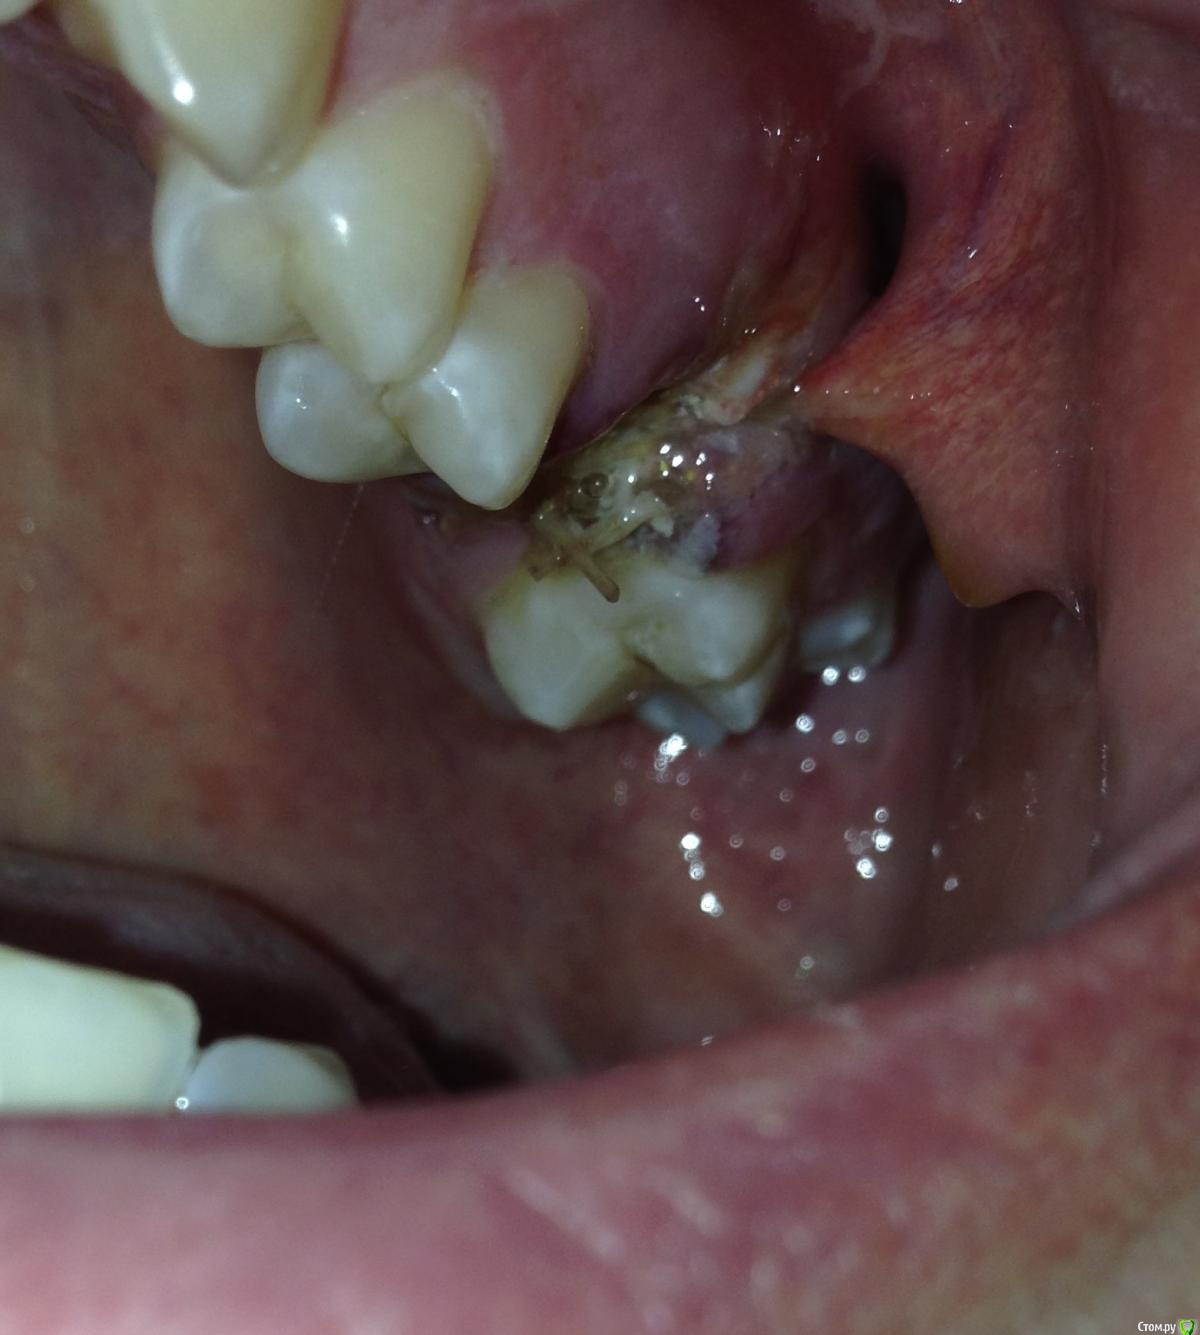

Евгений+ Опубликовано 14 октября, 2015 Автор Поделиться Опубликовано 14 октября, 2015 Доктор, сразу после удаления подсадил материал кости, поставил мембрану и ушил лунку рассасывющимися нитками.Но вот что странно, пришил еще щеку к десне - это норма??Я конечно не против, но предупредил бы хоть))) Ссылка на комментарий

red_butler Опубликовано 14 октября, 2015 Поделиться Опубликовано 14 октября, 2015 Но вот что странно, пришил еще щеку к десне - это норма?? покажите фото Ссылка на комментарий

Евгений+ Опубликовано 14 октября, 2015 Автор Поделиться Опубликовано 14 октября, 2015 Может я чего не понимаю, но отодрать не получилось)) - начинает кровить. Ссылка на комментарий

Евгений+ Опубликовано 17 октября, 2015 Автор Поделиться Опубликовано 17 октября, 2015 (изменено) Всем большое спасибо!Был у докторов, сказали ничего не делать рассосется и щека в порядке будет. Сегодня, на 5-й день, рассосалось 4 шва (тройка). Остатки швов аккуратно убрал, чтоб не мешали. Ничего не болит.Потом начала торчать, а вскоре и отвалилась мембрана 1х2 см. Выпало немного порошка костного.Так и должно быть??? Изменено 17 октября, 2015 пользователем Евгений+ Ссылка на комментарий